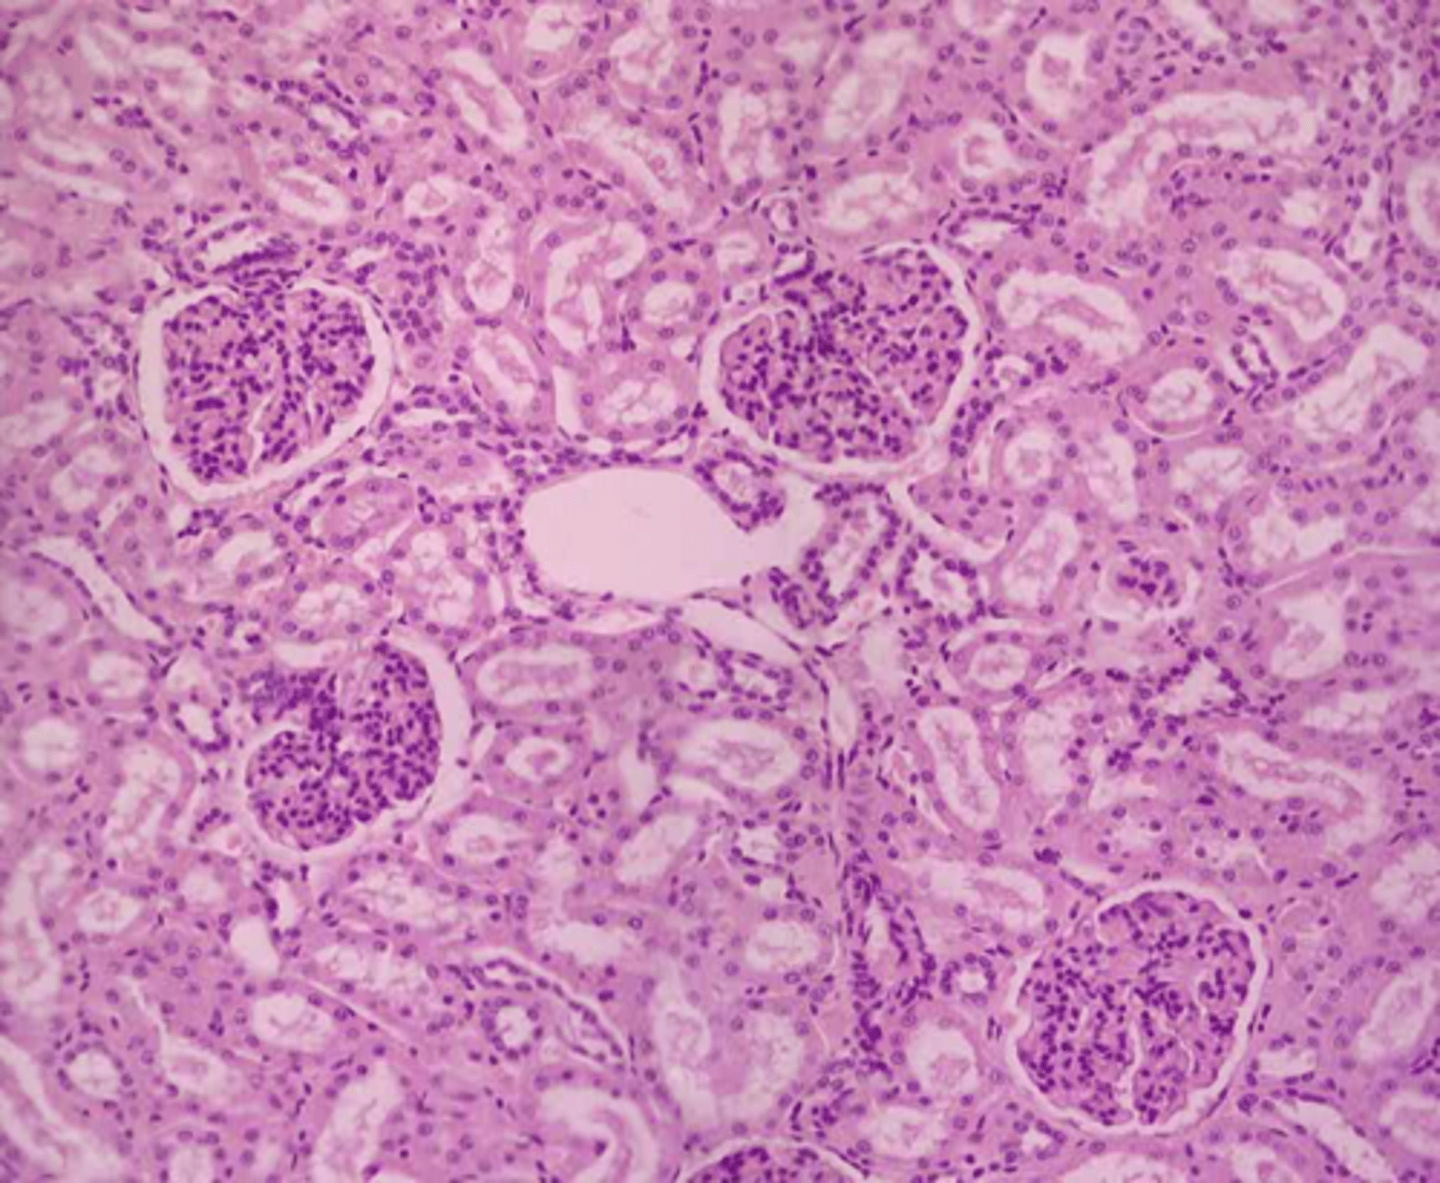

renal cortex tissue

identify renal corpuscle/renal tubule

macula densa

renal cortex (sheep)